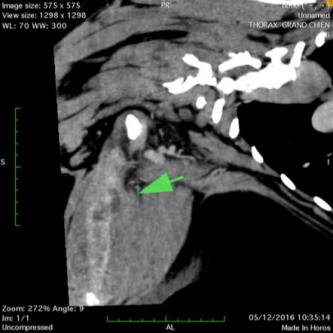

Les scanners thoraciques:

Cet examen est très utile en complément d'une radiographie. Il permet aussi de visualiser des lésions là l'echographie ne peut rien faire, comme par exemple  une recherche de lésion intra-pulmonaire.

L'examen va permet d'une part d'apprecier la structure interne de la lésion (et d'en determiner la nature) et d'autre part de la délimiter précisément en vue d'une chirurgie thoracique.